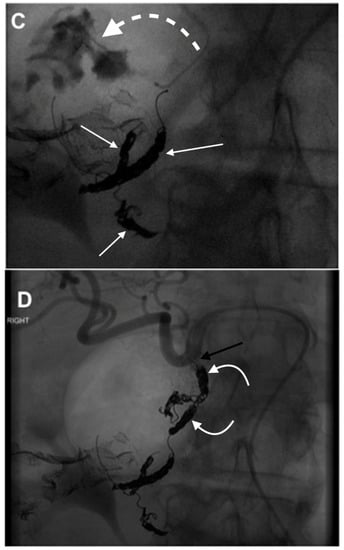

3. GDA Embolization in Gastrointestinal Bleeding